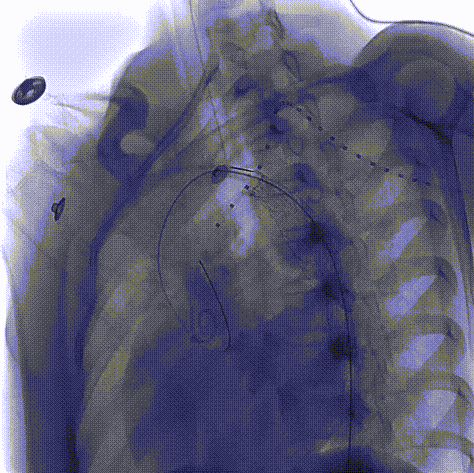

术前3D重建